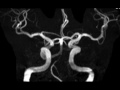

Persistent Trigeminal Artery

An anomalous vessel courses from the right cavernous internal carotid artery to the basilar artery. This is consistent with a persistent trigeminal artery, which represents the most common persistent carotid-basilar anastomosis.